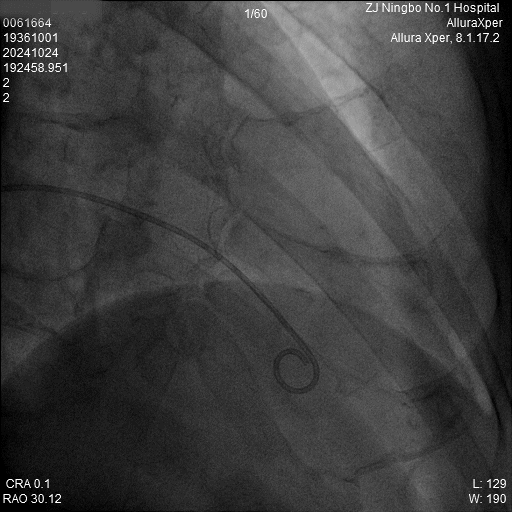

1.猪尾导管造影:软钢丝配合猪尾导管进入RV,造影显示RV轮廓。

a)RAO 30